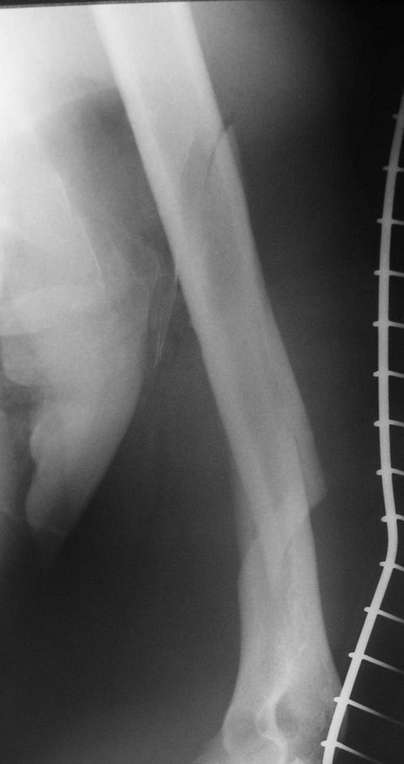

Красиво и быстро?! - две пластины + 18 шурупов.

Идеальная репозиция?! -На снимочке A-P проeкции видна "зазубрина" по суставной поверхности, латеральный снимок - тоже не идеально.

Множество мелких FB в кости.

Выписан через 3 дня после операции - как минимум,надо 7 дней i.v. антибиотикотерапию.

Даже если не возникнет септических осложнений, скорей всего исход - нетрудоспособность(disability).

IMHO- ПХО,активный дренаж, и если не аппарат наружной фиксации,то даже вытяжение за бугристость б/б кости.